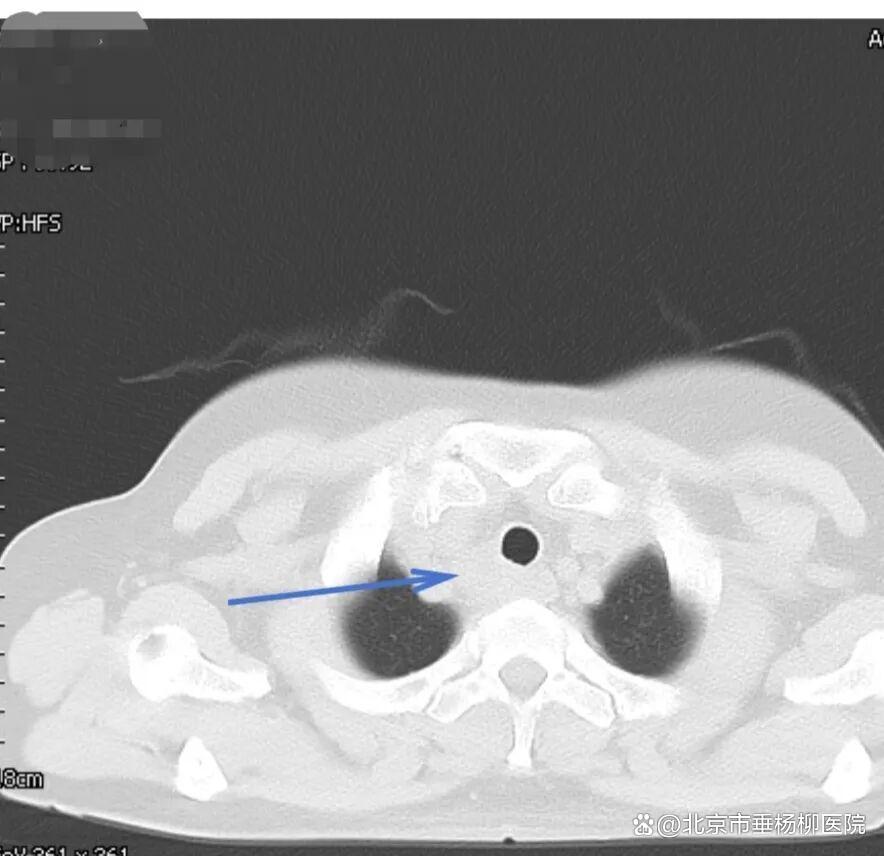

经过胸外科团队的成功采样,医院病理科专家当晚即对穿刺标本进行分析,镜下可见真菌菌丝,形态符合曲霉菌感染,未见恶性肿瘤细胞。“不是癌,是感染!”这个结果让所有人松了一口气。医疗团队随即为患者制定抗真菌治疗方案,经系统治疗后,患者吞咽哽咽感明显缓解,复查影像显示病灶显著缩小。

▲治疗后一个月胸部CT